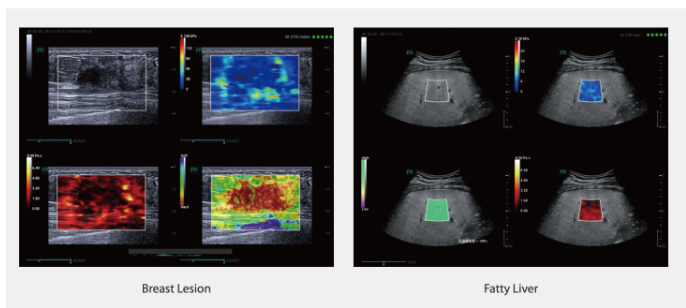

STVi

STVi позволяет проводить количественную оценку вязкости тканей и предоставляет возможность мультипараметрической визуализации в реальном времени, предлагая более комплексный подход к диагностике и количественному анализу хронических заболеваний печени, новообразований молочной железы и других патологий.

-

Два количественных коэффициента

-

Оценка хронических заболеваний печени

-

Множество инструментов количественного анализа

-

Оценка опухолей молочной железы

-

Новообразование молочной железы

-

Жировой гепатоз